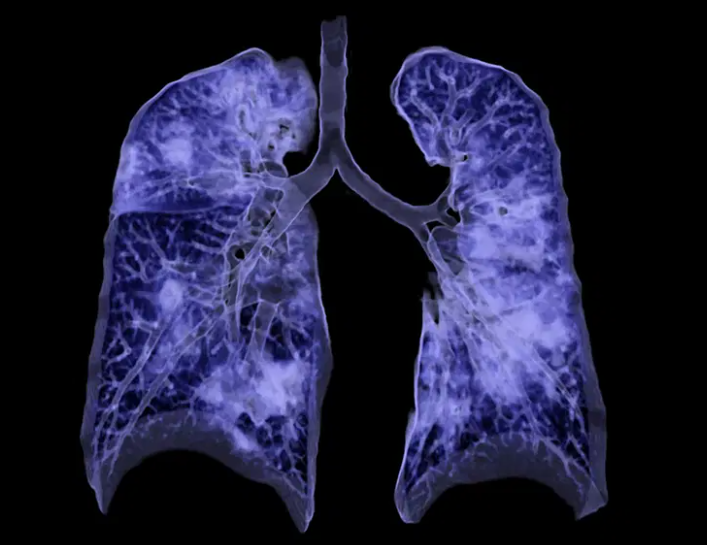

Quando o RX não esclarece completamente o quadro clínico ou há suspeita de complicações, a TC de alta resolução (TCAR) entra em cena. Ela permite observar com riqueza detalhes como espessamento septal, opacidades em vidro fosco, nódulos pulmonares, destruição alveolar e alterações brônquicas.

Com cortes finos e reconstruções multiplanares, é o exame de escolha para avaliar a extensão de uma fibrose, o padrão intersticial, ou confirmar/emergir lesões compatíveis com sequelas da COVID-19. Também auxilia no estadiamento de neoplasias pulmonares e investigações vasculares (angio-TC).

- DPOC: hiperinsuflação, achatamento diafragmático, rarefação de trama vascular.

- Fibrose pulmonar: espessamento septal, faveolamento, bronquiectasias por tração.

- Sequelas de COVID-19: vidro fosco, consolidações residuais, fibroses.